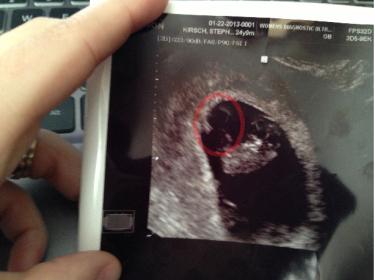

These were u/s pic taken at 8+3. This was a transvaginal u/s. Can you tell me what you think baby's sex is based on the Ramzi Theory?

boy, only assuming the image isn't flipped.

Let's assume that it wasn't flipped. I think im confused on how Ramzi works. I thought it was the side the yolk sac/placenta was on, not the side the baby is on? So in this picture it would be on the left? That was confirmed the cord, according to the tech.

I went by where I thought I saw the placenta

I'm not great at this though, and admittedly your image was hard to go off. It looks sideways to me.